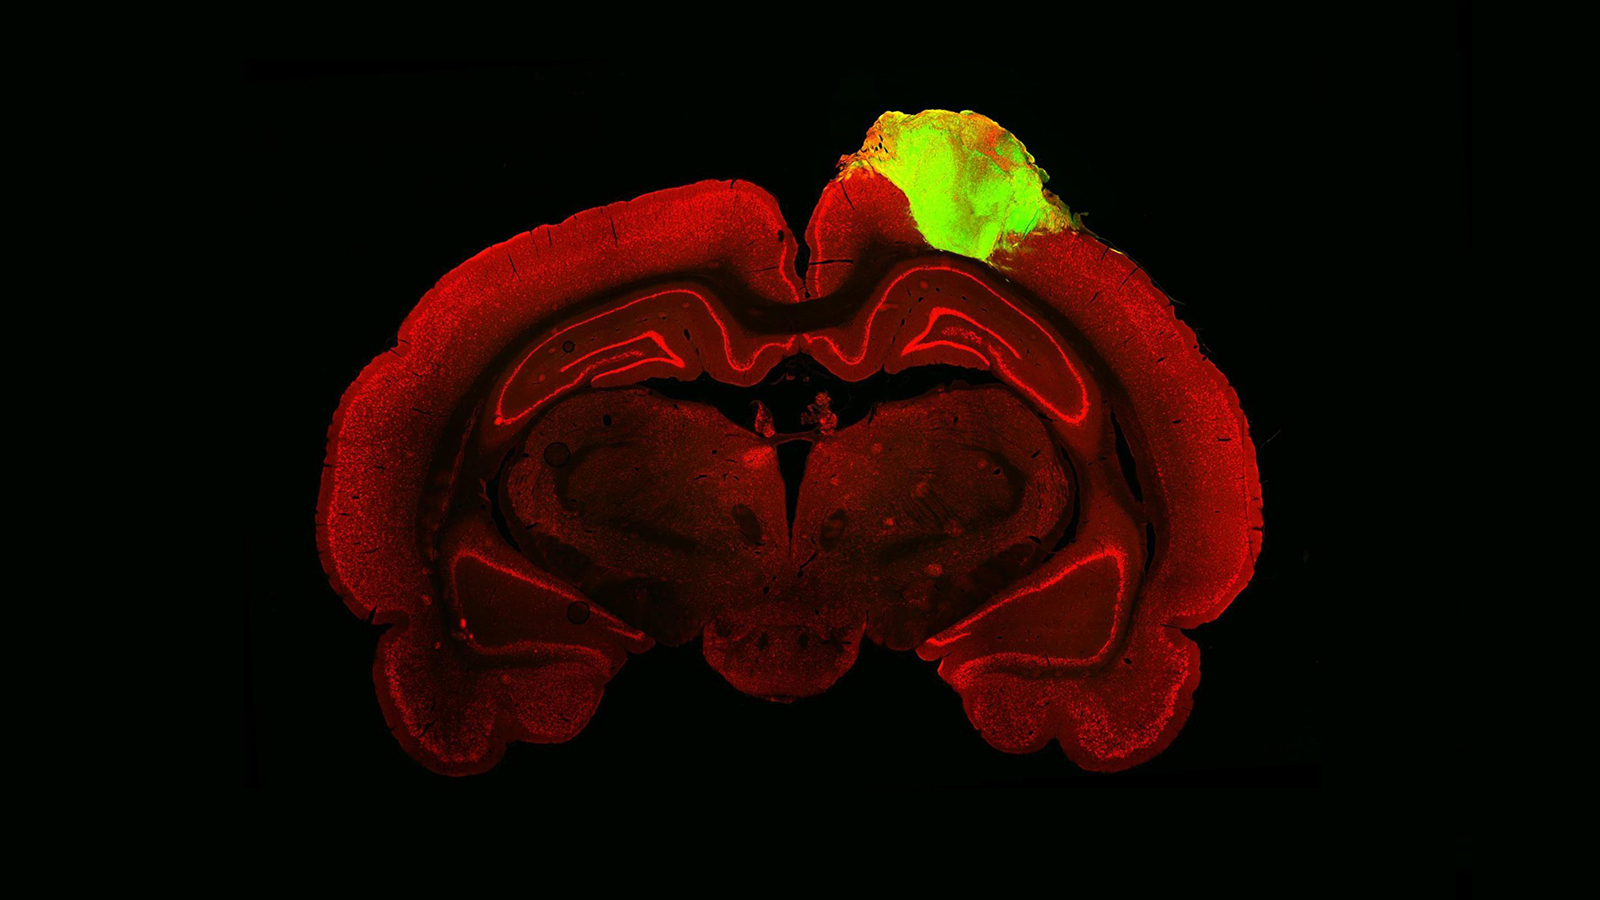

Human-rat brain hybrid shows a way to cure blindness

New research has shown that human “mini brains” can integrate with damaged rat brains to perform functions related to sight.